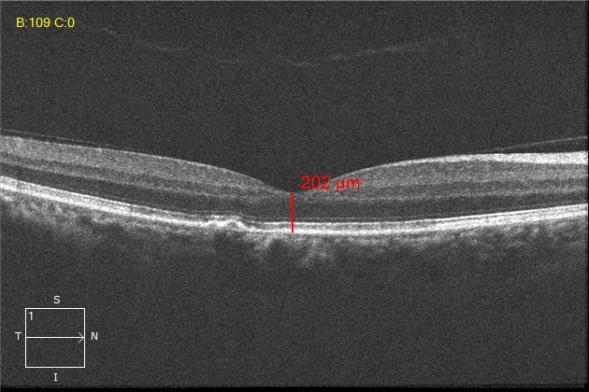

中浆oct图片,中浆oct

型眼底彩照:黄斑区颜色变暗,像中心凹色红周边有光晕这个病简称中浆

中浆oct

中浆oct的详细图解

中浆病的oct检查图